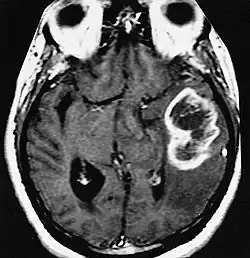

| MRI showing a ring-enhancing lesion in the brain of a patient with glioblastoma multiforme | |

| Differential diagnosis | CNS lymphoma and CNS toxoplasmosis |

A ring-enhancing lesion is an abnormal radiologic sign on MRI or CT scans obtained using radiocontrast. On the image, there is an area of decreased density (see radiodensity) surrounded by a bright rim from concentration of the enhancing contrast dye. This enhancement may represent breakdown of the blood-brain barrier and the development of an inflammatory capsule. This can be a finding in numerous disease states. In the brain, it can occur with an early brain abscess as well as in Nocardia infections associated with lung cavitary lesions. In patients with HIV, the major differential is between CNS lymphoma and CNS toxoplasmosis. CT imaging is the appropriate next step to differentiate between the two conditions.[1]